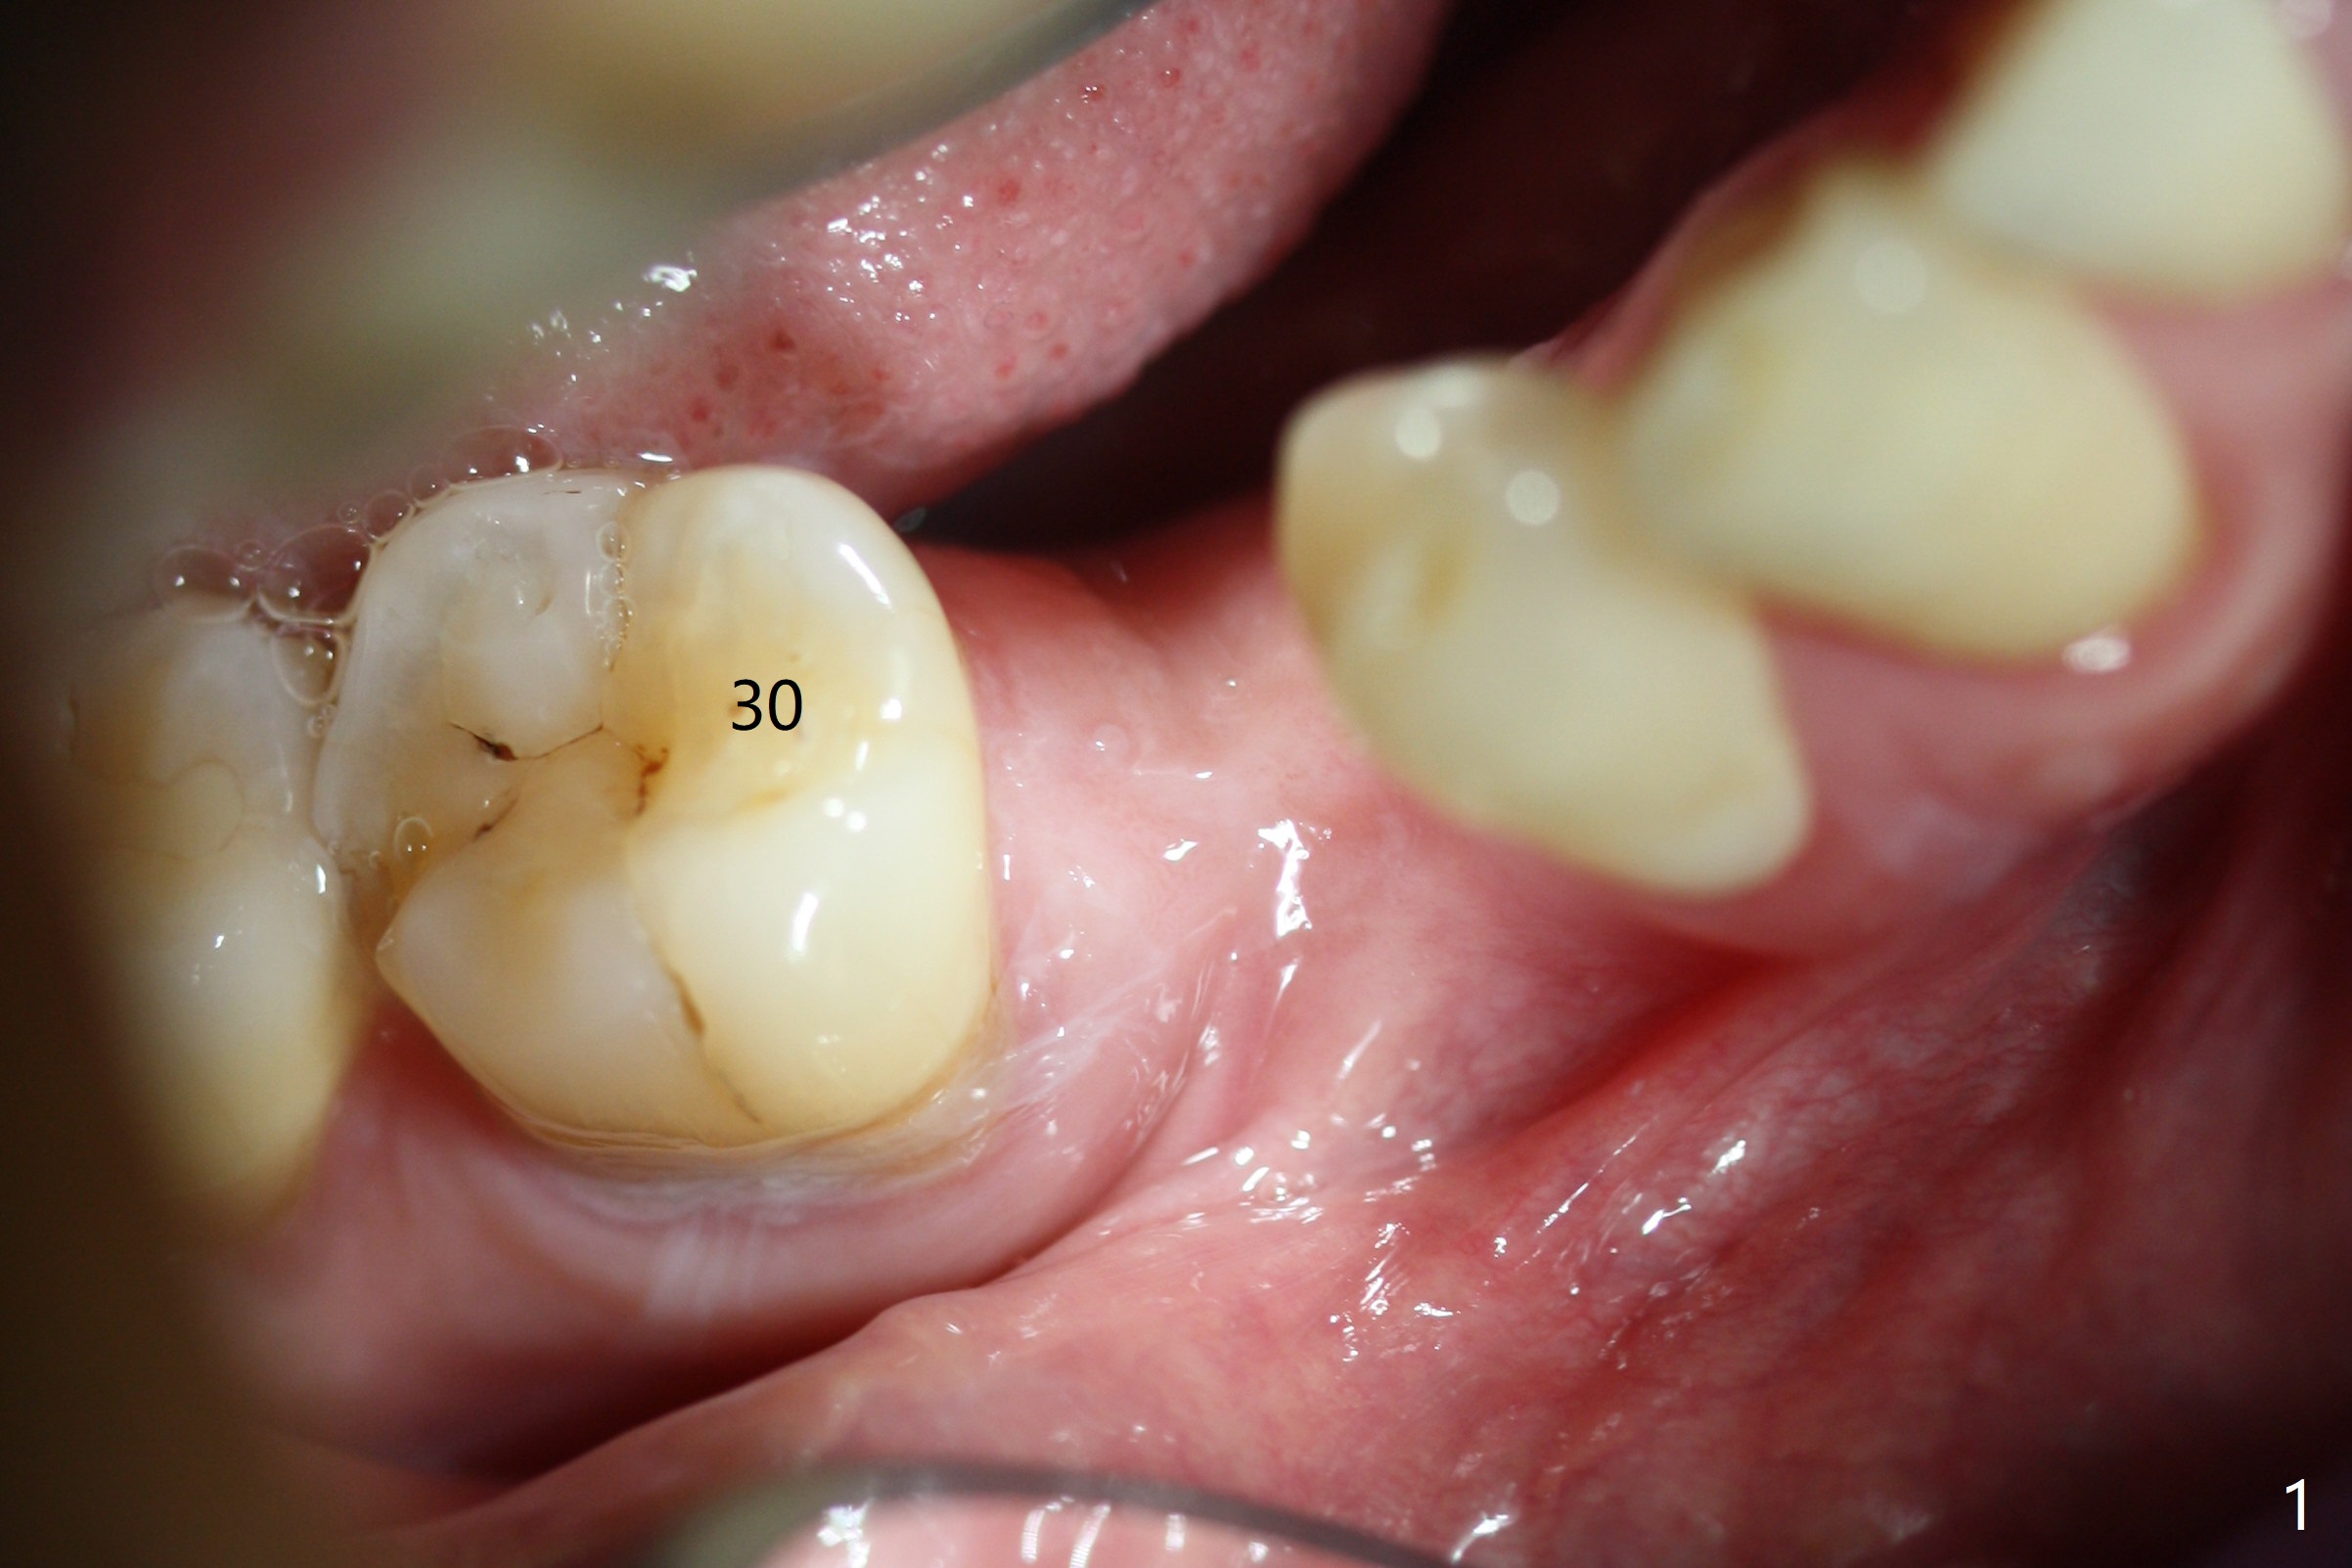

The base of the edentulous ridge at #29 looks wide (Fig.1), but the most coronal portion is the thin soft tissue (Fig.2). It appears that there has been bone resorption since extraction. The initial osteotomy depth is 11.5 mm (Fig.3). Since the Mental Loop seems to be nearby, the depth of subsequent osteotomy (3 mm) remains the same (Fig.4). Although the final depth of osteotomy is 13 mm, the implant placed is short (3.8x11.5 mm, Fig.5,6), as compared to the immediate implant (3.8x18 mm) at the contralateral side (#20). There is mild bone resorption mesially 4 months postop (Fig.7). The crown is loose (poor osteotomy position, guide necessity) 7 months post cementation immediately prior to 18 cementation, although there is no gross bone losss 1 year 7 months post cementation (Fig.8).